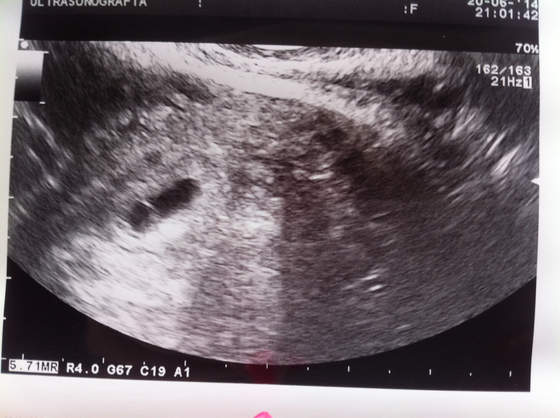

Przedstawiam wam mojego obcego :)

Zobacz załącznik 630110

jak na 5 tydzień ciąży to jest wszystko na swoim miejscu i odpowiedniej wielkości , dr pytał sie nas czy na pewno 1 zarodek dostaliśmy :) ale o tym przekonamy sie za tydzień na wizycie juz z serduszkiem :) rano mam taką w klinice a na wieczornej randce z Dr prowadzącym, dostałam wczoraj juz zwolnienie , wiec oficjalnie JESTEM W CIĄŻY :)